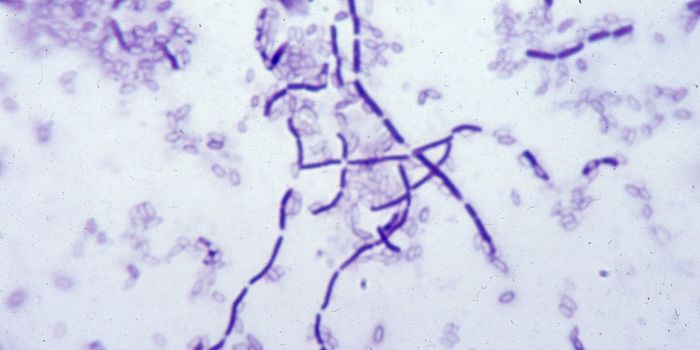

JAN 31, 2016MicrobiologyResearchers at the University of Notre Dame identified the mechanism by which Streptococcus pyogenes, also known as Grou ...